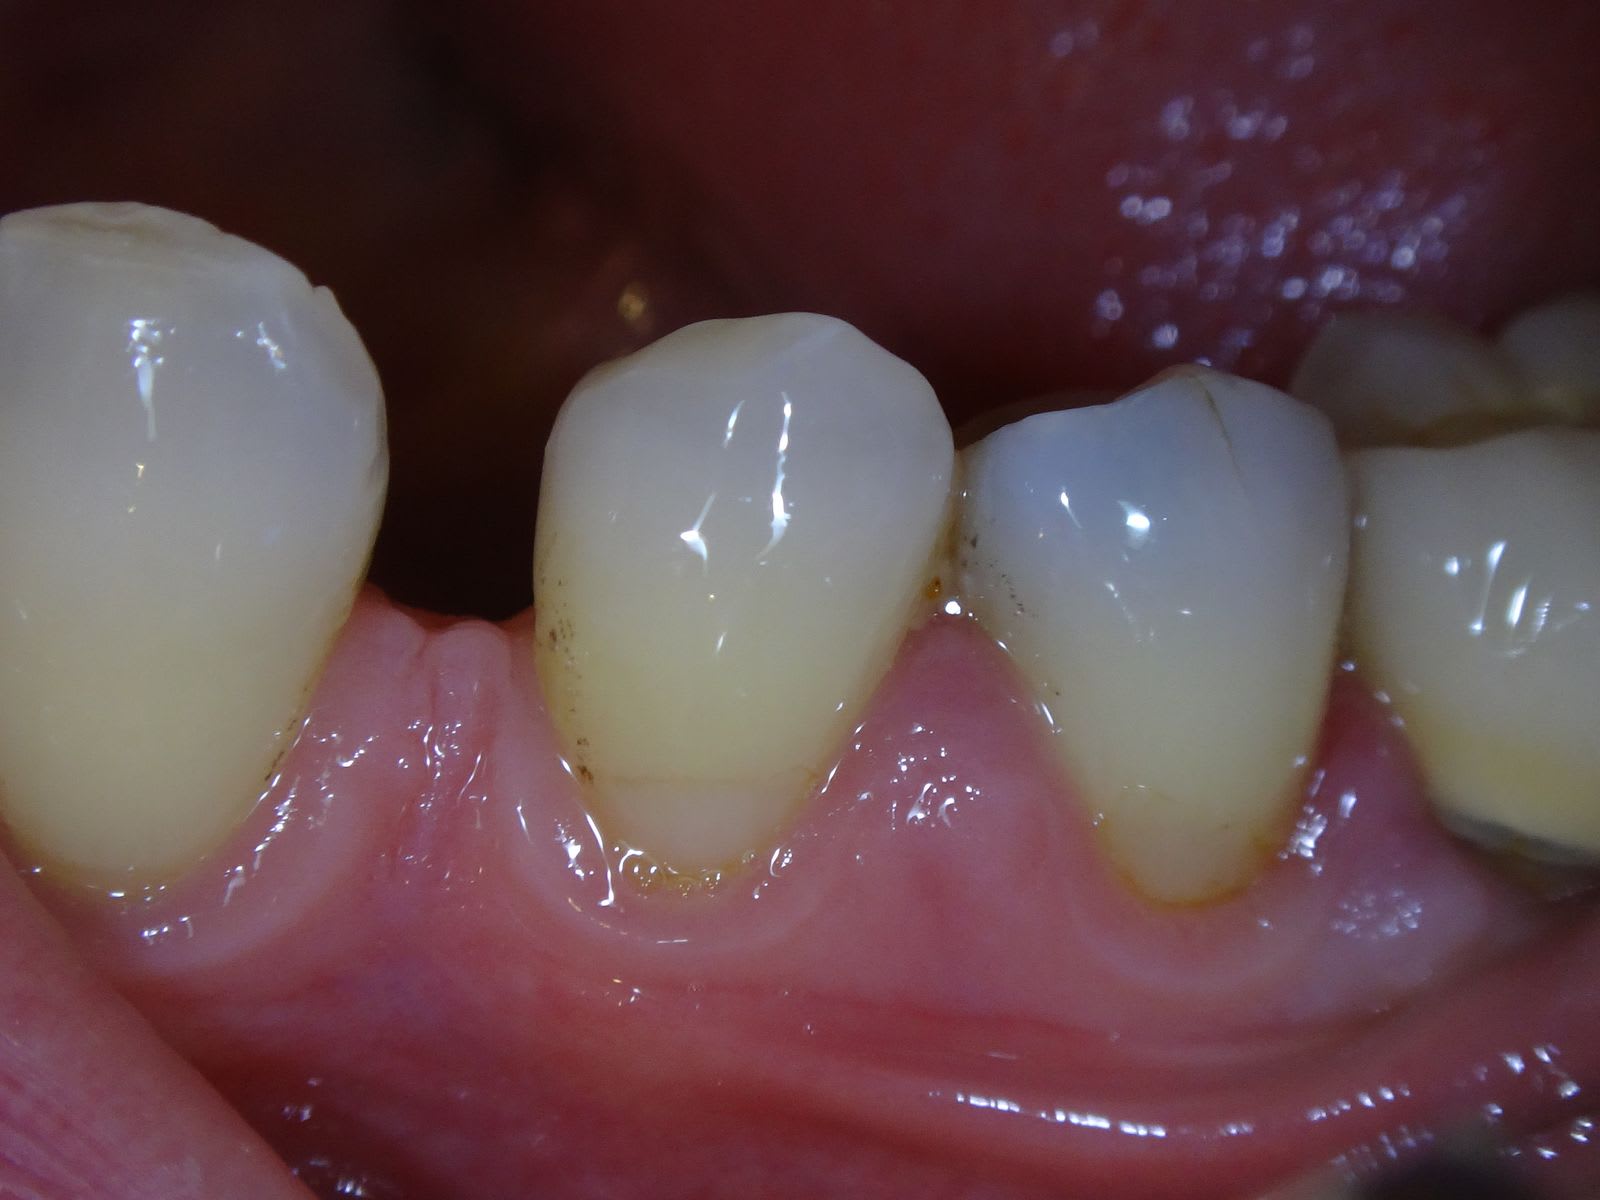

N'empêche qu'avec un simple téléphone portable, on peut prendre des photos qui rendent pas si mal que ça :

-> y a juste un inconvénient, c'est que les secteurs latéraux sont flous avec un téléphone portable. Mais qu'est-ce que c'est plus pratique que les appareils à plusieurs milliers d'euros...

Photo d'un téléphone :